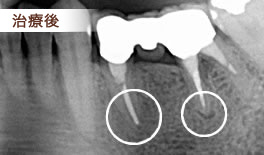

主訴 根尖病巣の治療

根尖病巣内の細菌を根管経由で採取して専用のチェアーサイド嫌気培養器で培養を行い 無菌になるまで消毒を繰り返します。

無菌になったことを確認して、根管内に根管充填剤を充填して治療を終了します。

根管内の消毒を繰り返すも、なかなか無菌にならないことで通常の根管治療では成功率が落ちることがわかり、根管内嫌気培養の必要性の意味が深く理解できてこの治療を受けてよかった実感される方が多いです。